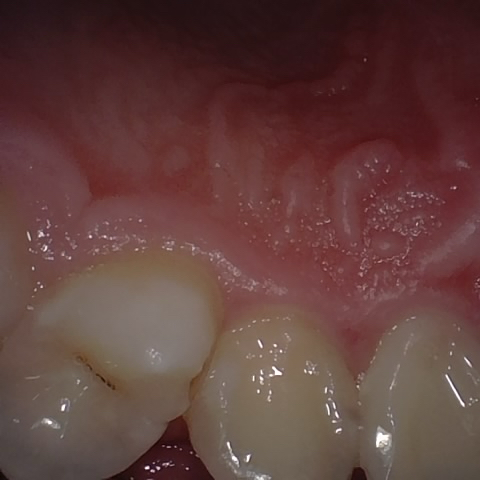

Annotated as "Good"